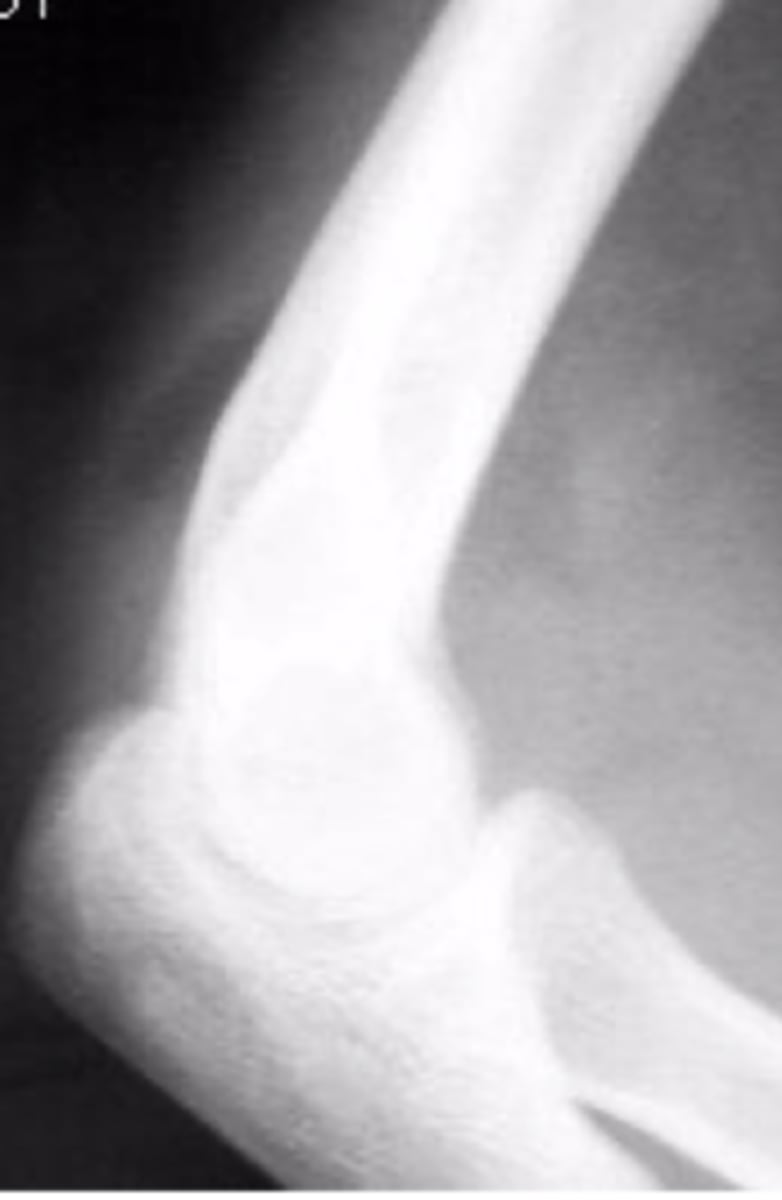

abnormal supinator sign

What is the issue?